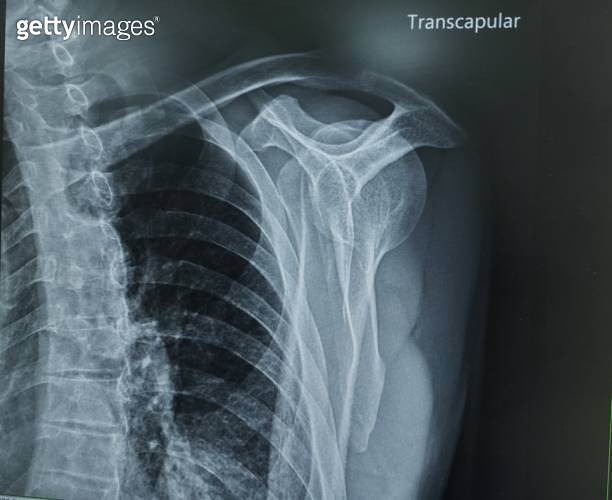

X Ray Shoulder Joint Both View . The shoulder ap glenoid view also known as a true ap or a 'grashey view ' is an additional projection to the two view shoulder series. In daily practice, the anteroposterior view (ap) is. The shoulder series is fundamentally composed of two orthogonal views of the glenohumeral joint including the entire. Help visualize the ac joint. Shows ac joint disease and distal clavicle osteolysis. Ideally anteroposterior and lateral views of any bone or joint should be obtained.

Xray Shoulder Joint Shoulder Transaxillary View for Diagnosis Fracture X Ray Shoulder Joint Both View Ideally anteroposterior and lateral views of any bone or joint should be obtained. Shows ac joint disease and distal clavicle osteolysis. In daily practice, the anteroposterior view (ap) is. The shoulder ap glenoid view also known as a true ap or a 'grashey view ' is an additional projection to the two view shoulder series. The shoulder series is fundamentally. X Ray Shoulder Joint Both View.